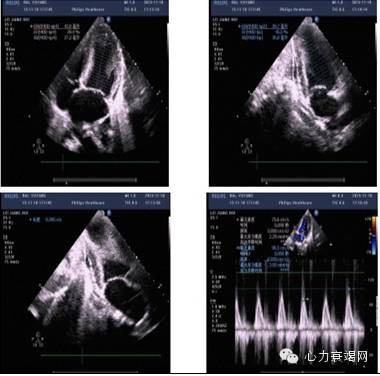

辅助检查:心动超声(11-18)

超声提示:EF值 42%(M型Teich公式法);45%(双平面Simpson’s法)